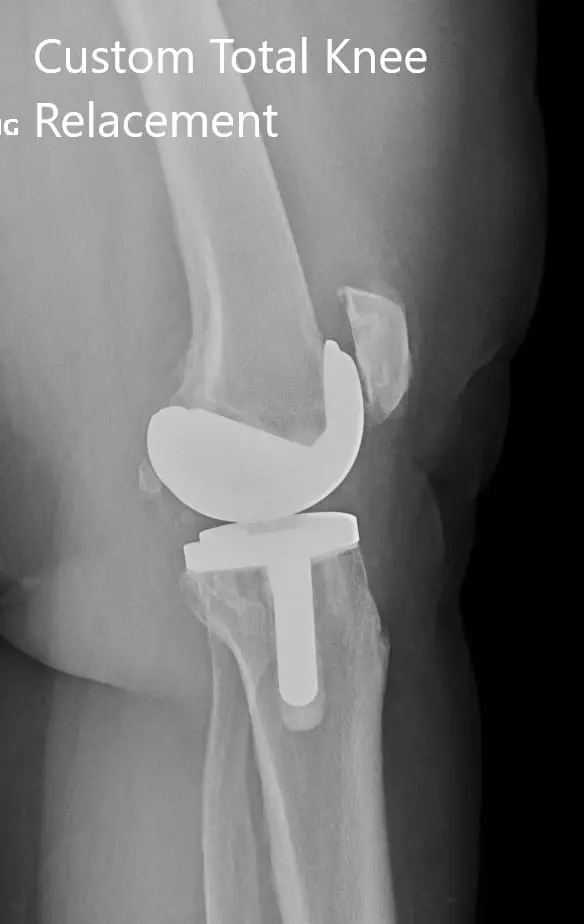

Postoperative X-ray showing the lateral views of both knees.

IMPLANTS USED: Customized knee replacement systems left and right. Bilateral polyethylene size 8 mm and patella size 32 mm x 6 mm.